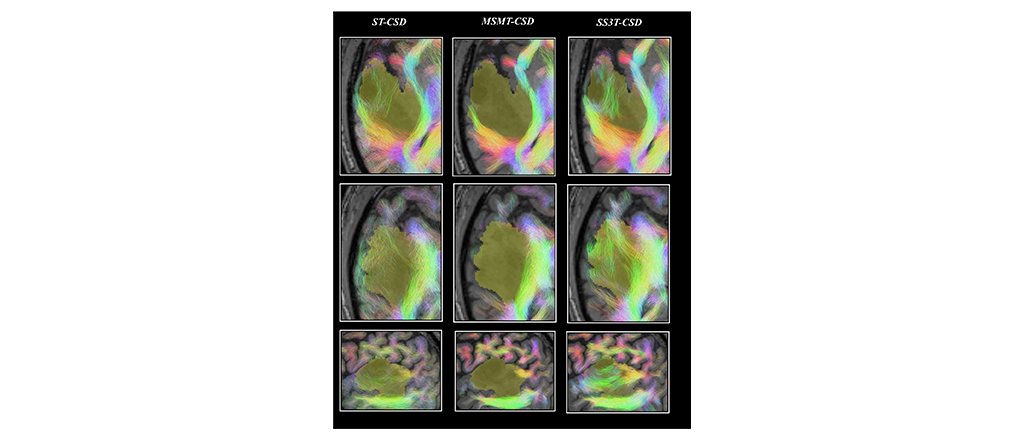

Comparison of tractography results based on single tissue (ST)-CSD, Multi Shell Multi Tissue (MSMT)-CSD and Single Shell 3 Tissues (SS3T-CSD)34 pipelines for patient PAT26 (anaplastic astrocytoma WHO grade III)